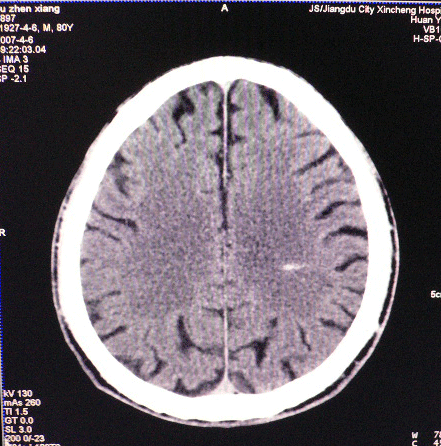

以下是引用dyqct在2007-4-8 16:25:00的发言:[br]支持左侧放射冠区少量出血。

以下是引用狙击手在2007-4-8 22:45:00的发言:[br]出血?从患者的症状考虑病灶应该在左侧大脑半球的基底节区或颞顶部,如此小的病灶引起上述症状的可能性不大,患者可能有梗塞(时间短,目前ct还看不见)或是tia发作,再者像这样的线条形出血的确不多见,但还是有可能的,曾经碰到有外伤类似出血,复查后消失,所以还是慎重一点,短期复查即可。